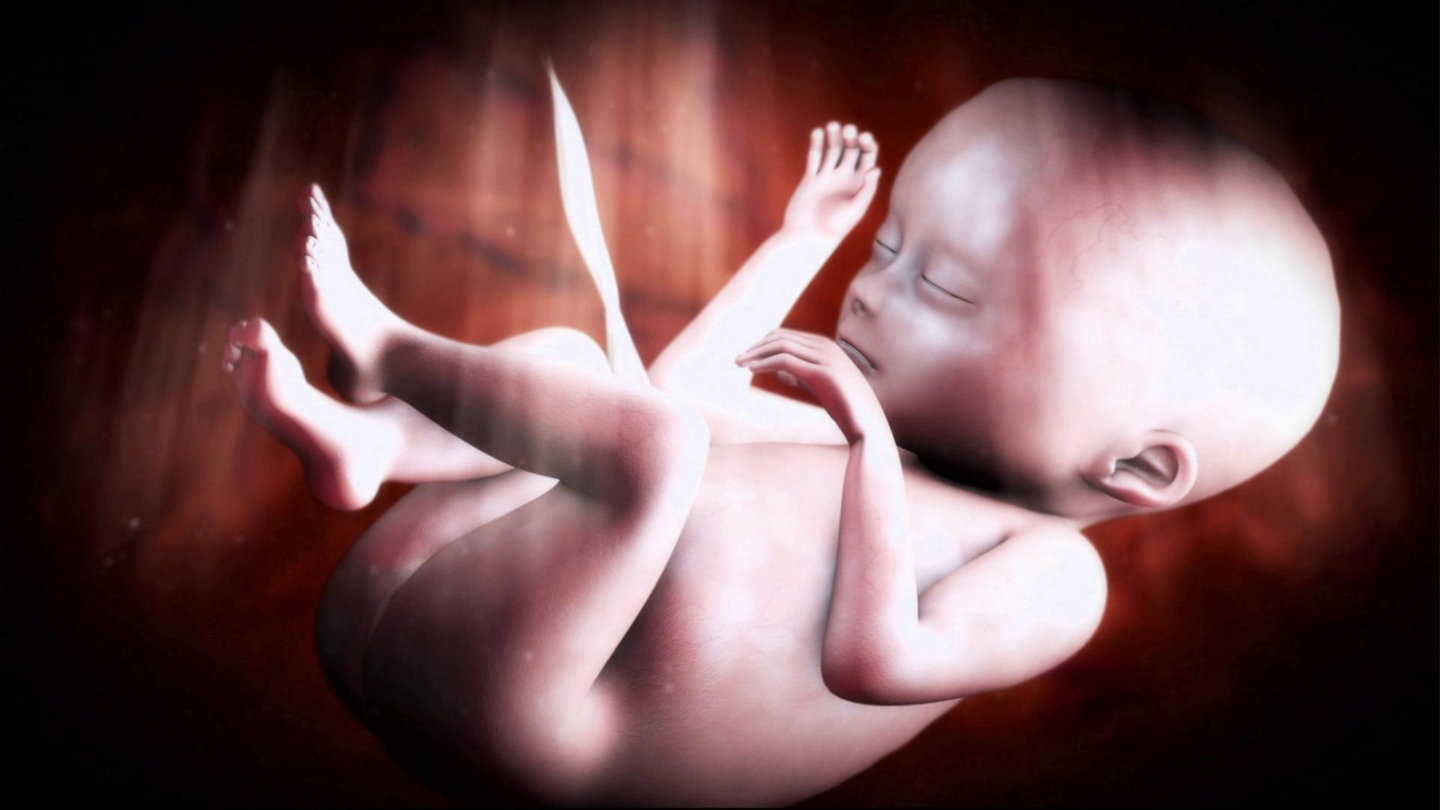

Wie finden sich Spermium und Eizelle? Wann werden im Embryo welche Organe angelegt? Wie verändert sich der Fötus im Verlauf der neunmonatigen Schwangerschaft? Dieser Film porträtiert die Entstehung menschlichen Lebens von der Befruchtung bis zur Geburt.

Wir begleiten die schwangere Sabrina und ihre kleine Tochter Ronja auf ihrem Weg zu Ultraschalluntersuchungen, Schwangerschaftsgymnastik. Mit Sabrina gehen wir dann in den Kreißsaal. Aufwändige Computer-Animationen zeigen die Anatomie der Geschlechtsorgane, illustrieren die Arbeitsweise von Nabelschnur und Plazenta und veranschaulichen ausgewählte Entwicklungsschritte des Kindes im Mutterleib.